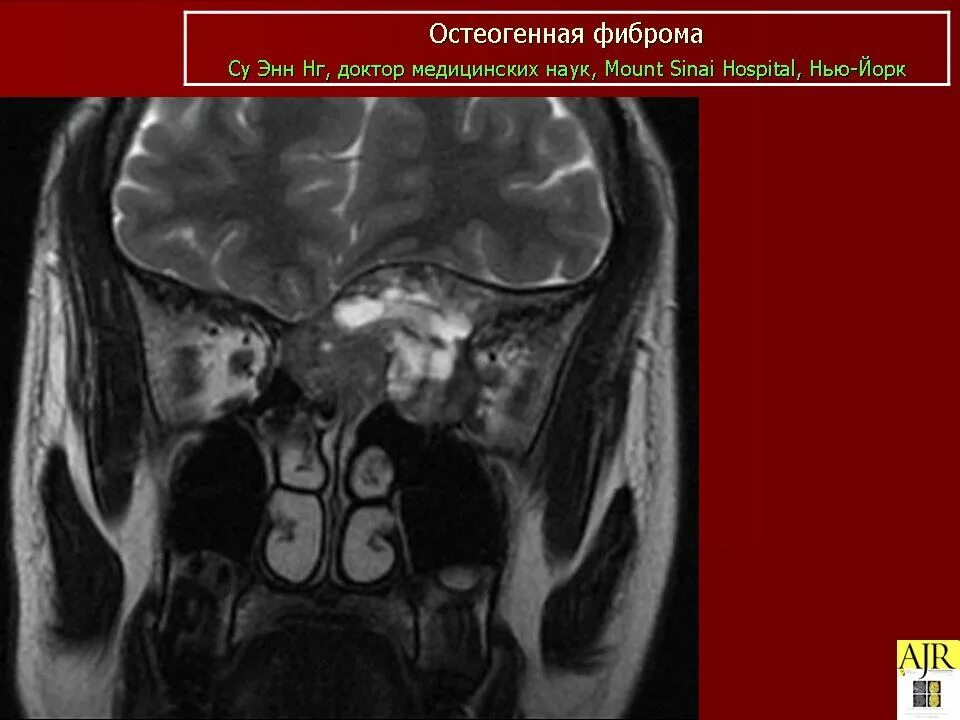

Фиброма кт